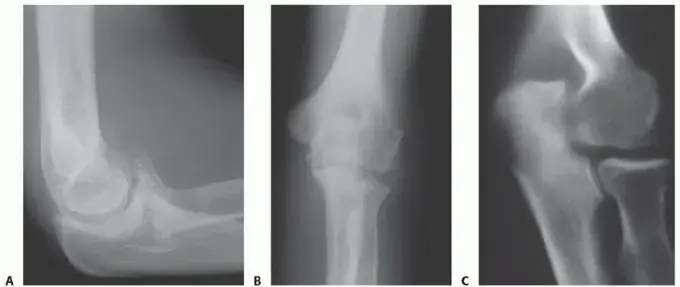

المفاصل المستهدفة في جراحة الاستبدال

الحديث عن استبدال المفاصل في اليد يركز بشكل أساسي على نوعين من المفاصل التي غالبًا ما تتأثر بالالتهابات والتآكل:

1. المفاصل السنعية السلامية (Metacarpophalangeal Joints - MCP):

• الموقع: هي المفاصل التي تربط عظام المشط (في راحة اليد) بالسلاميات القريبة (أول عظم في الإصبع). هذه هي المفاصل التي تشكل "براجم" الأصابع (knuckles).

• الوظيفة: تسمح هذه المفاصل بثني وفرد الأصابع بشكل كبير، بالإضافة إلى حركات التباعد والتقريب (فصل وضم الأصابع). إنها حيوية للقدرة على الإمساك بالأشياء وتشكيل قبضة قوية.

• لماذا تتأثر؟ غالبًا ما تكون المفاصل السنعية السلامية هي الأكثر عرضة للضرر والتورم والتشوه في حالات مثل التهاب المفاصل الروماتويدي.

2. المفاصل السلامية القريبة (Proximal Interphalangeal Joints - PIP):

• الموقع: هي المفاصل الواقعة في منتصف كل إصبع (بين السلامية القريبة والسلامية الوسطى).

• الوظيفة: تسمح هذه المفاصل بشكل أساسي بالثني والفرد، وهي ضرورية للحركات الدقيقة مثل الكتابة، التقاط الأشياء الصغيرة، أو العزف على الآلات الموسيقية.

• لماذا تتأثر؟ بينما تتأثر بشكل أقل شيوعًا بالروماتويد مقارنة بمفاصل MCP، إلا أنها غالبًا ما تكون المتضرر الرئيسي في حالات خشونة المفاصل (التهاب المفاصل التنكسي) والتهاب المفاصل الصدفي.